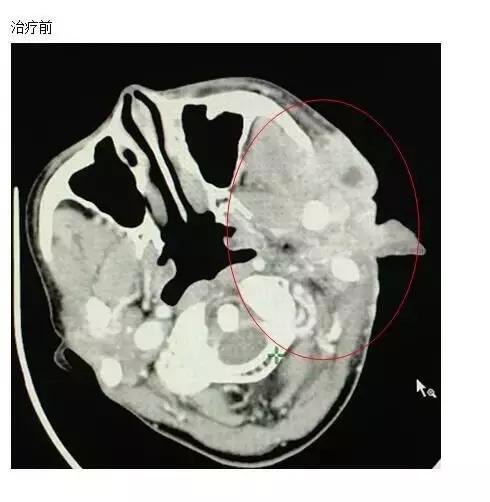

A45治疗前

吴女士的发病毫无征兆,两年前一次无意中在脸上摸到肿物,到医院检查后,被确诊为腺泡细胞癌,随即前往国内权威肿瘤医院进行手术切除患侧腮腺,并行瘤床及高危淋巴结引流区放疗30次。本以为可以逃过一劫,不料,术后半年腮腺癌就复发了,肿瘤比原来的还要大,二次手术后不到两个月,右耳前皮下再次出现肿物,并逐渐增大,右耳前皮肤开始出现水泡,后逐渐增多,多次复发的她已对治疗失去了信心,甚至想放弃治疗。家人的支持让她重拾信心,慕名找到全球肿瘤医生网,在前往苏州大学附属肿瘤医院接受治疗前的检查,发现肺部也出现转移灶,她抱着试试看的心情接受了A45肿瘤动力治疗,经过全身和局部的A45肿瘤动力治疗后,病灶缩小非常明显,皮肤逐渐愈合好转。